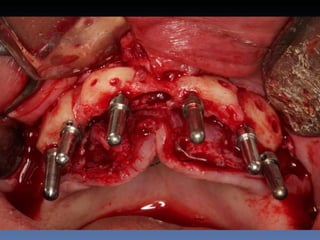

BOX 1

Sônia Elizabete Correa

Idade – 58 anos

Sexo – Feminino

Raça – Caucasiana

ASA – II

Data- 27-04-2012

Diagnóstico: Desdentada total da maxila com

atrofia severa

Plano de tratamento: Reabilitação com 4 implantes

Zigomáticos – “All-on-four Zigoma”.